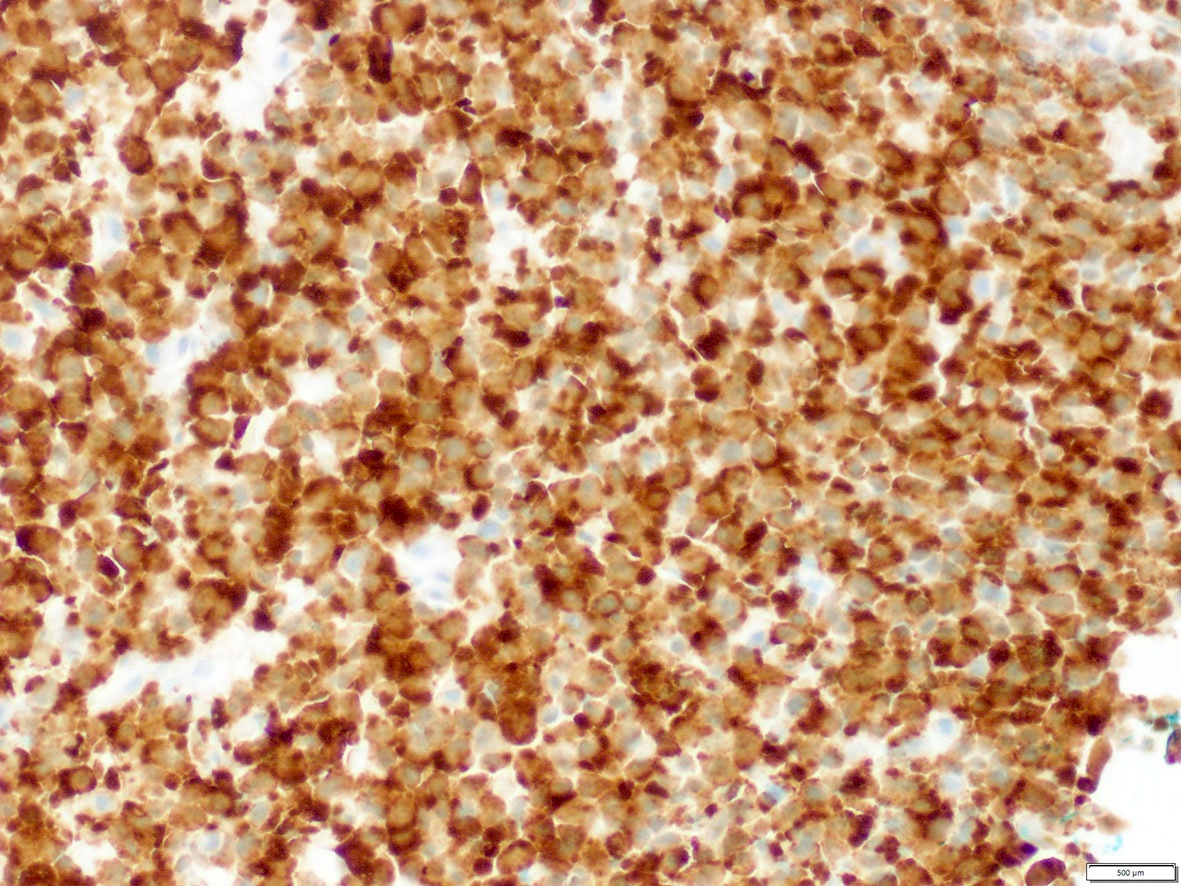

Microscopic (histologic) images

Contributed by A. Cristina Vargas, M.B.B.S., Ph.D., Patricia Guzman, M.D., Fiona Bonar, M.B.B.Ch., Alison Cheah, M.B.B.S. and Martin Jones, M.B.B.S.

Positive staining - disease

- ALK overexpression as a result of gene translocations / fusions:

- 50% of inflammatory myofibroblastic tumors (IMT) (Am J Surg Pathol 2015;39:957)

- Diffuse cytoplasmic expression: identified with the following fusion partners: EML4, ATIC, TFG, TPM4, MYH9, ALO17, TRAF1, PABPC1, EEF1G; CLTC-ALK fusion shows cytoplasmic granular / dotted pattern (Semin Diagn Pathol 2020;37:57, Am J Surg Pathol 2017;41:25)